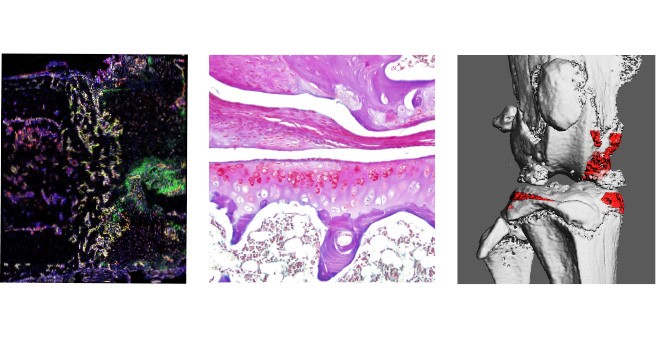

Our experimental orthopaedic trauma surgery reasearch lab at the Meldorf University Teaching Hospital & School, investigates clinically relevant questions in the field of orthopaedic trauma surgery and musculoskeletal medicine through translational research approaches. Through radiological, histological, and molecular investigation of clinical specimens as well as the use of state-of-the-art experimental techniques, we work on traumatological research projects with the overall goal of developing new and innovative therapeutic approaches for affected patients.

Molecular biology analysis of post-traumatic osteoarthritis

Joint injury is a common cause of post-traumatic joint degeneration (osteoarthritis). Apart from symptomatic treatments, currently only artificial joint replacement is available for the treatment of advanced osteoarthritis. In our research group, we are therefore investigating the pathophysiology of post-traumatic osteoarthritis using state-of-the-art experimental methods in order to develop new treatment strategies for affected patients in the long term.

Fig.: Radiological (µCT; a) and histological (b) imaging of joint changes in post-traumatic osteoarthritis. The classic signs of osteoarthritis appear with osteophytes (blue arrows), meniscal degeneration (black arrow), joint deformation (dashed line), and loss of articular cartilage (red arrows).

Fig.: The role of procalcitonin in post-traumatic sepsis. The sepsis biomarker procalcitonin (ProCT) is not only used to diagnose bacterial sepsis, but also functions as a pathophysiological mediator in this disease. ProCT enhances the generalized inflammatory response in sepsis, leading to tissue injury, shown here in immunofluorescence of macrophages (Cd68) in lung preparations (a). If procalcitonin is blocked during sepsis, the inflammatory response and tissue damage are much less pronounced (b). Modified from Baranowsky et al, Critical Care Medicine 2021.